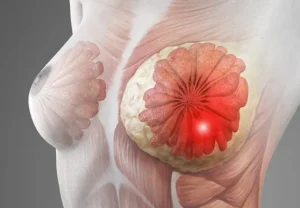

سرطان الثدي نوع من السرطان يبدأ على هيئة نمو للخلايا في نسيج الثدي. ويأتي سرطان الثدي بعد سرطان الجلد من حيث كونه أكثر أنواع السرطان